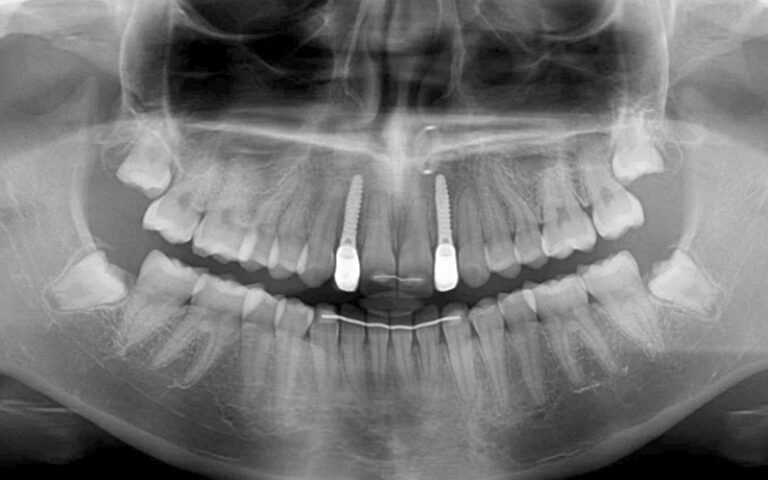

X-ray images of the revision at 6 months post-placement of the implants and 2 months after prosthetic load X-ray images of the revision at 6 months post-placement of the implants and 2 months after prosthetic load